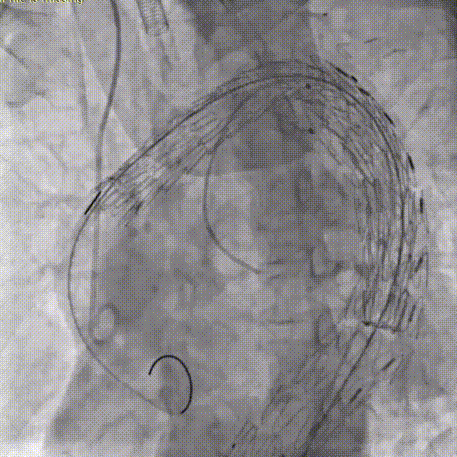

9.送入CADS支架TGM343420至主动脉弓,MPA导管送至升主动脉瘤体处(备弹簧圈和胶体),造影确认CADS准确定位于INA后缘。

CADS第一步释放,支架从近段向远端打开,释放至50%直径,造影确认调整支架近端位置,精准定位于INA远端。

CADS第二步释放,支架从远端向近端打开,释放至全直径;随后可以选择性调整近端成角,优化小弯侧贴壁。